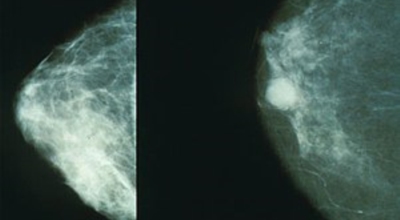

개인마다 유방암 초기증상은 다르게 나타날 수 있어요. 유방암은 우리나라 여성암 1위인만큼 많은 여성분들이 유방암 초기증상에 대해 관심이 많아 검사를 많이 하는 추세입니다. 스트레스를 많이 받는 젊은 여성들도 유방 통증으로 진단을 받는 경우가 늘고 있다고 하죠. 경우에 따라서는 유방암 초기증상이 없을 수도 있답니다. 유방암 자가검진 후 증상이 발견된다면 빨리 병원에 방문하는 것이 좋아요.

보통 자신의 인체사이즈 가슴의 크기가 빠르게 변화하지는 않습니다. 또한 좌우가 완벽하진 않아요. 하지만 대체적으로 대칭에 가까운 밸런스를 유지해요. 그러나 유방암 초기증상이 나타나게 되면 한쪽 가슴이 유독 부풀거나 및 가슴 형태가 조금은 예전과는 다르고 다른 한쪽과 다른 느낌이 든다면 초기증상일수 있다고 하네요.